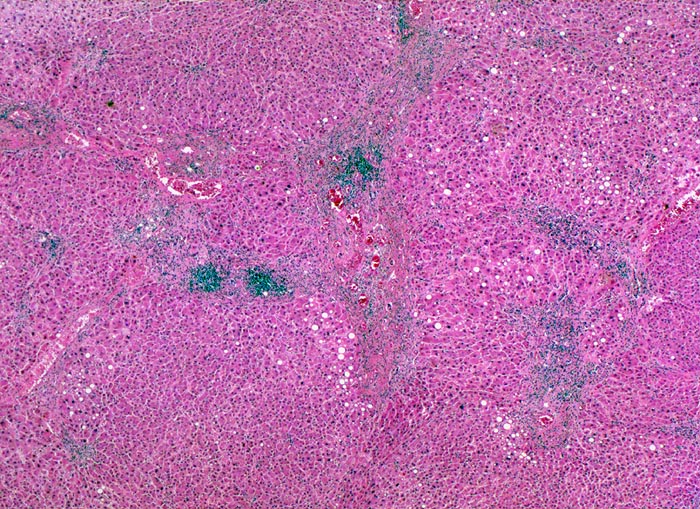

chronische Hepatitis C mit minimaler Aktivität

Der Verlauf der Portalfelder ist an dichten lymphoiden Entzündungsinfiltraten erkennbar, welche zum Teil gebogen verlaufen. Dieser Verlauf deutet auf eine portoportale fibröse Septenbildung hin. Ein vollständiger zirrhotischer Umbau mit Knotenbildung liegt noch nicht vor.

Patient mit bekannter chronischer Hepatitis C. Bei einer sonographischen Kontrolluntersuchung wird ein 1cm grosser Knoten entdeckt. Das Alpha-Fetoprotein im Serum ist nicht erhöht.

Das Ausmass der Fibrose wird bei chronischen viralen Hepatitiden als Staging angegeben. Dieses reicht von einer leichten Bindegewebsvermehrung in den Portalfeldern über eine portoportale Septenbildung und einen unvollständigen zirrhotischen Umbau bis zur voll etablierten Zirrhose. Es existieren verschiedene Grading- und Staging Systeme für die Bestimmung des Schweregrades einer chronischen viralen Hepatitis. Vor allem das Ausmass der Fibrose ist entscheidend für die Therapieindikation.